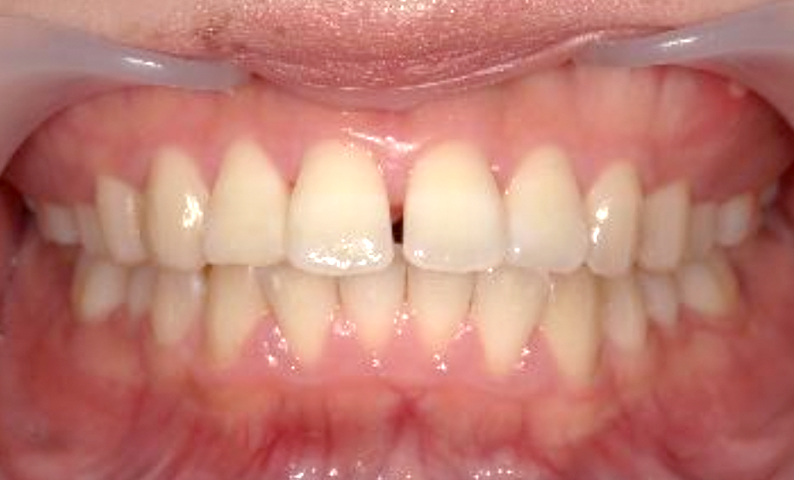

| 治療前 | 治療後 |

|---|---|

|